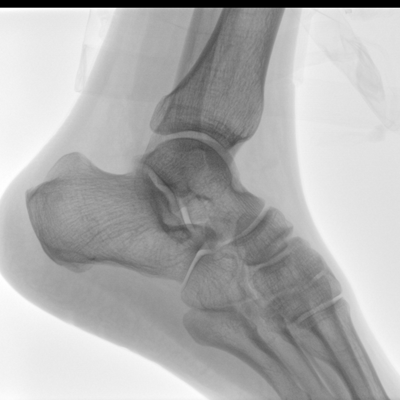

大尺寸液晶顯示器,圖像顯示清晰細(xì)膩;顯示器可大角度旋轉(zhuǎn),滿足臨床多角度觀察圖像的需要。